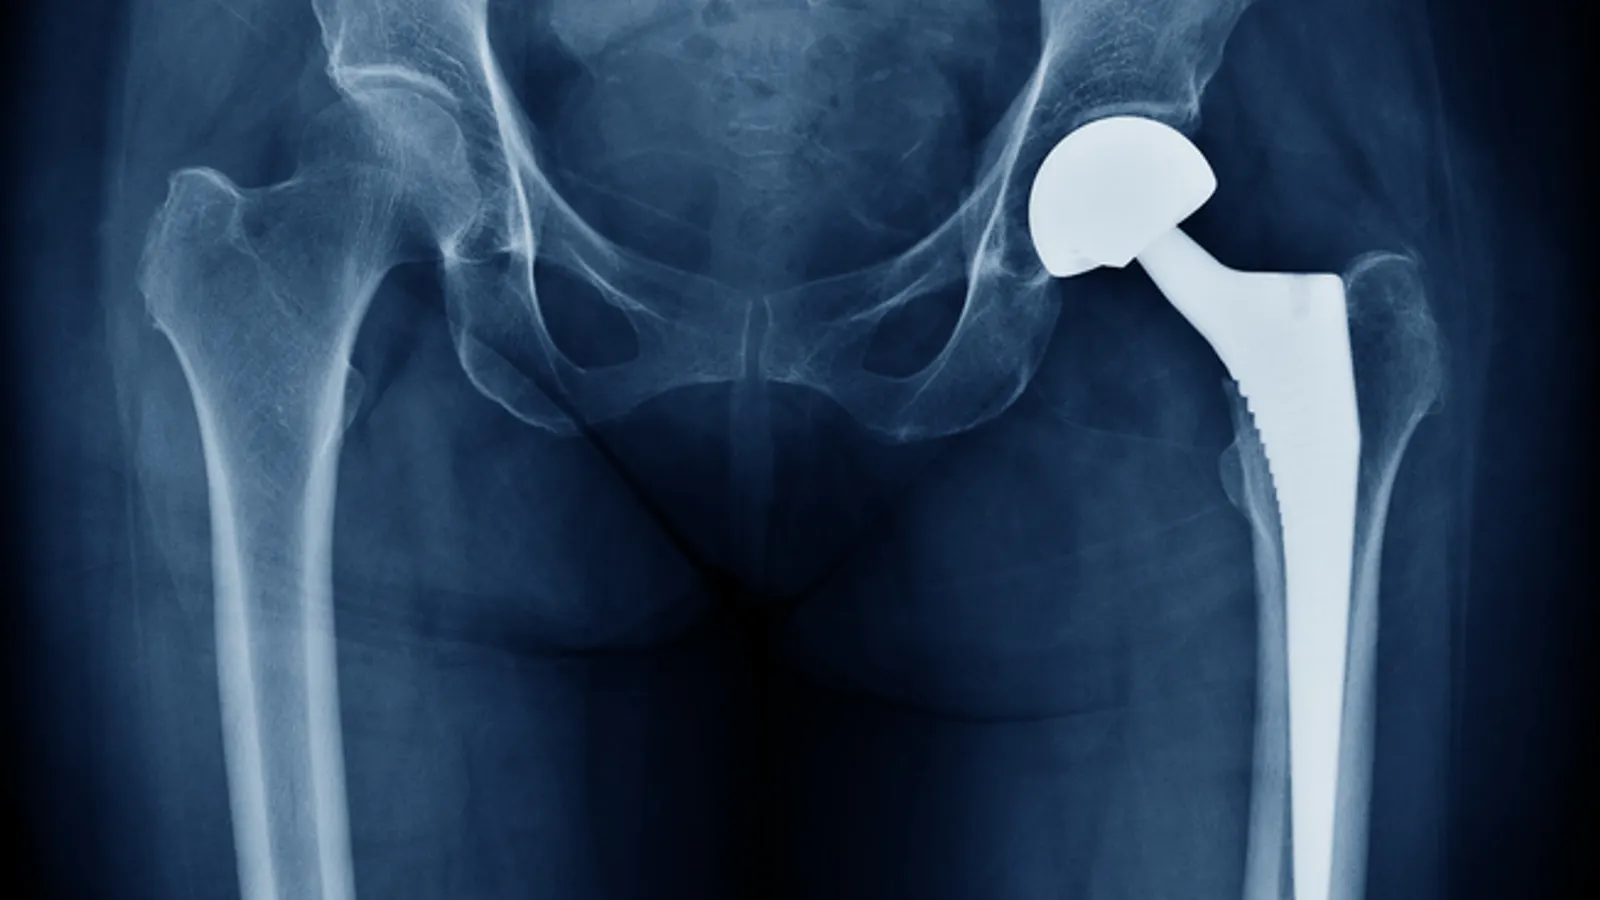

CEO Ivan Tornos said multiple factors emerged late in the quarter that caused the shortfall. Zimmer’s shares plunged more than 15%.